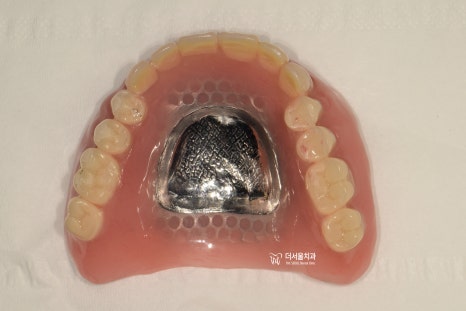

『틀니 치료 결과』

틀니를 장착 했을 때,

첫번째로 고려해야 될 것은

‘편안함’ 입니다.

연조직이랑 맞닿아서 유지력을 얻기 때문에

정말 신중히 제작을 해야 되는데

첫번째 단계는 바로 indivisual tray 를

만드는 겁니다.

환자마다 가지고 있는 악궁의 형태가

다 다르기 때문에 개인에게 딱 맞는

본을 뜰 수 있는 손잡이가 필요한거죠.

이렇게 만들어드린 뒤에, 인상 채득을 거쳐

사진에서 보실 수 있는 것 처럼

상악 전체 틀니가 완성이 됩니다.

물론, 사전에 색조 대조는 합니다.

어떤 색조로 틀니를 만들어야 되는지

미리 색조를 결정해두는 겁니다.

(shade taking)